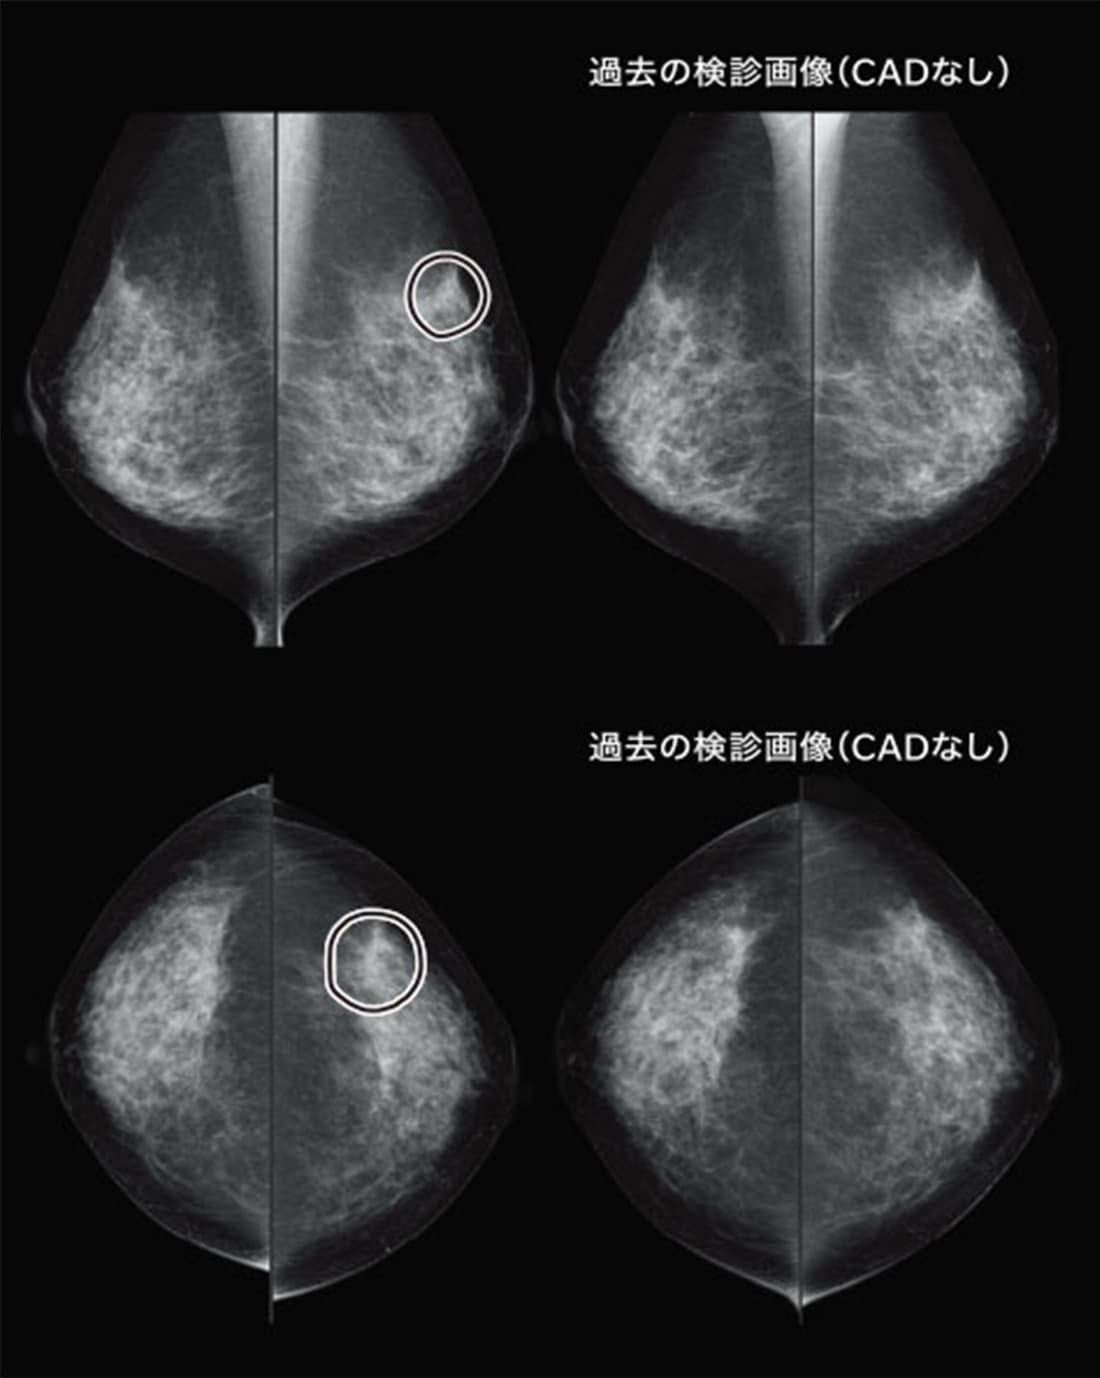

【症例4】 Distortion

左外上部が気になるかと思いますが、CADもDistortionを正しく指摘しています。比較読影でも濃度の上昇がみとめられました。このような陰影をCADは読み落とさずに検出しており、開発当初に比べると性能がかなり上がっています。